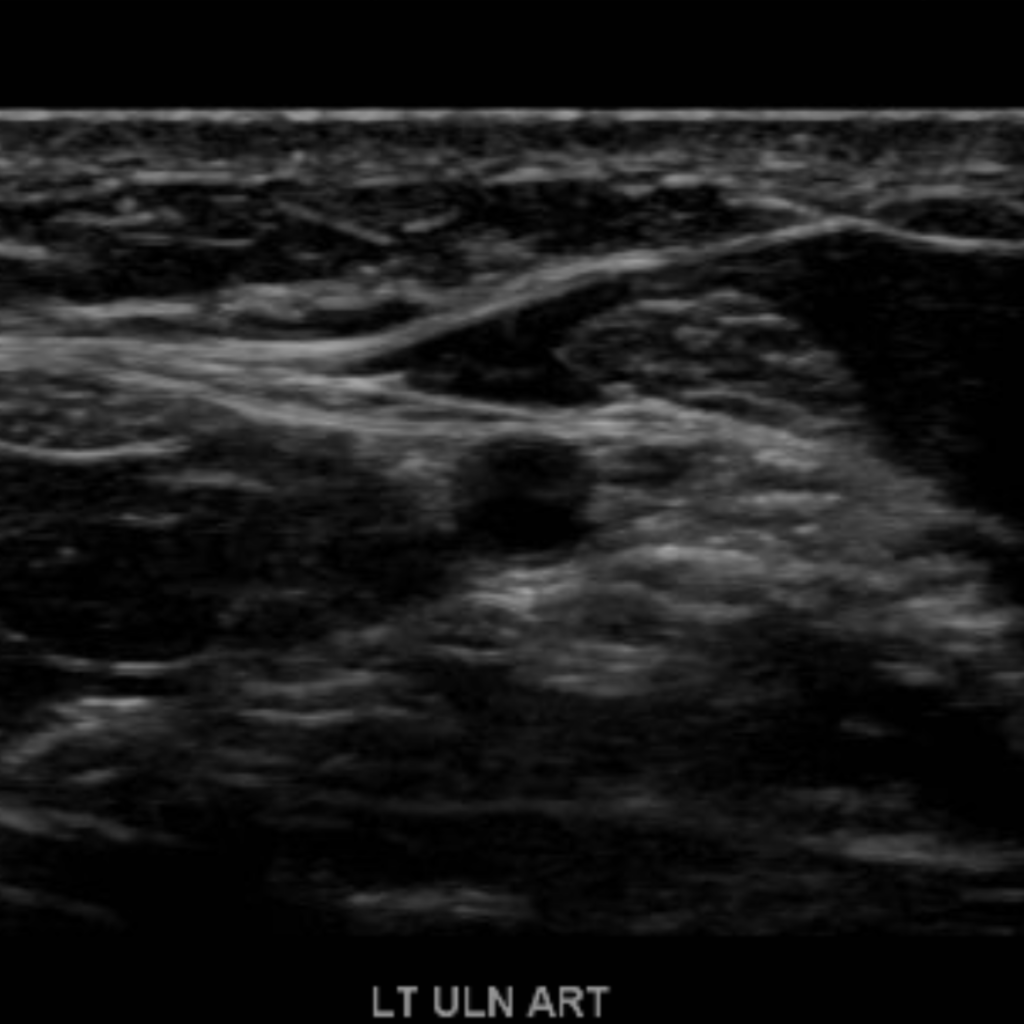

The subclavian artery arises from the brachiocephalic artery on the right and off of the aortic arch on the left. This artery further divides into the axillary, brachial, radial, ulnar, palmar and digital arteries respectively.